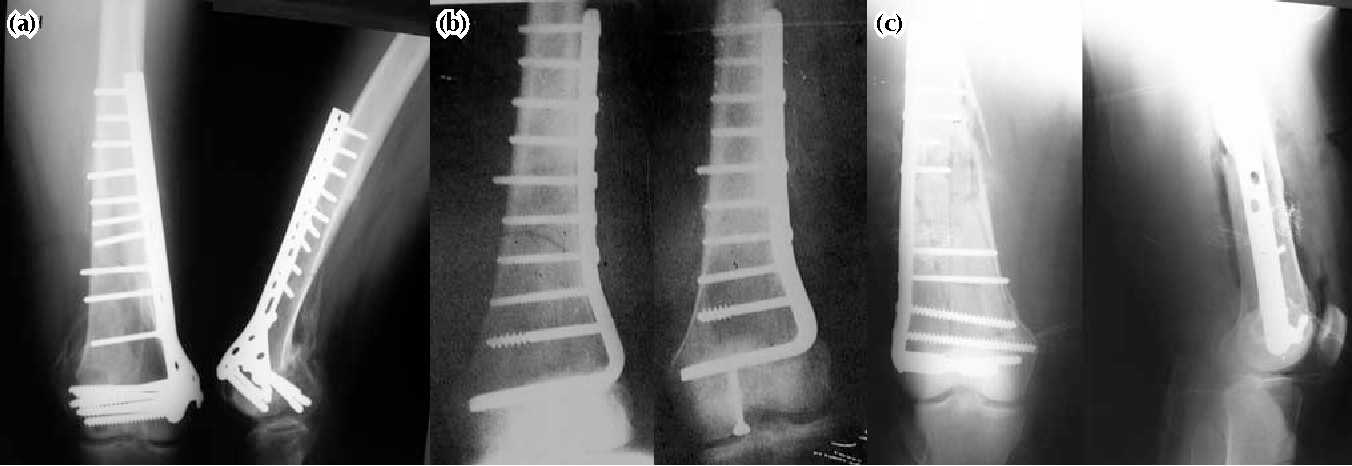

Operative treatment with internal fixation can enable accurate fracture reduction, especially of the joint surface, and early movement.

a) Intramedullary fixation.

b) Blade plate fixation.

c) Dynamic condylar screw.

d) Condylar locking screw.

e) Double plate fixation.